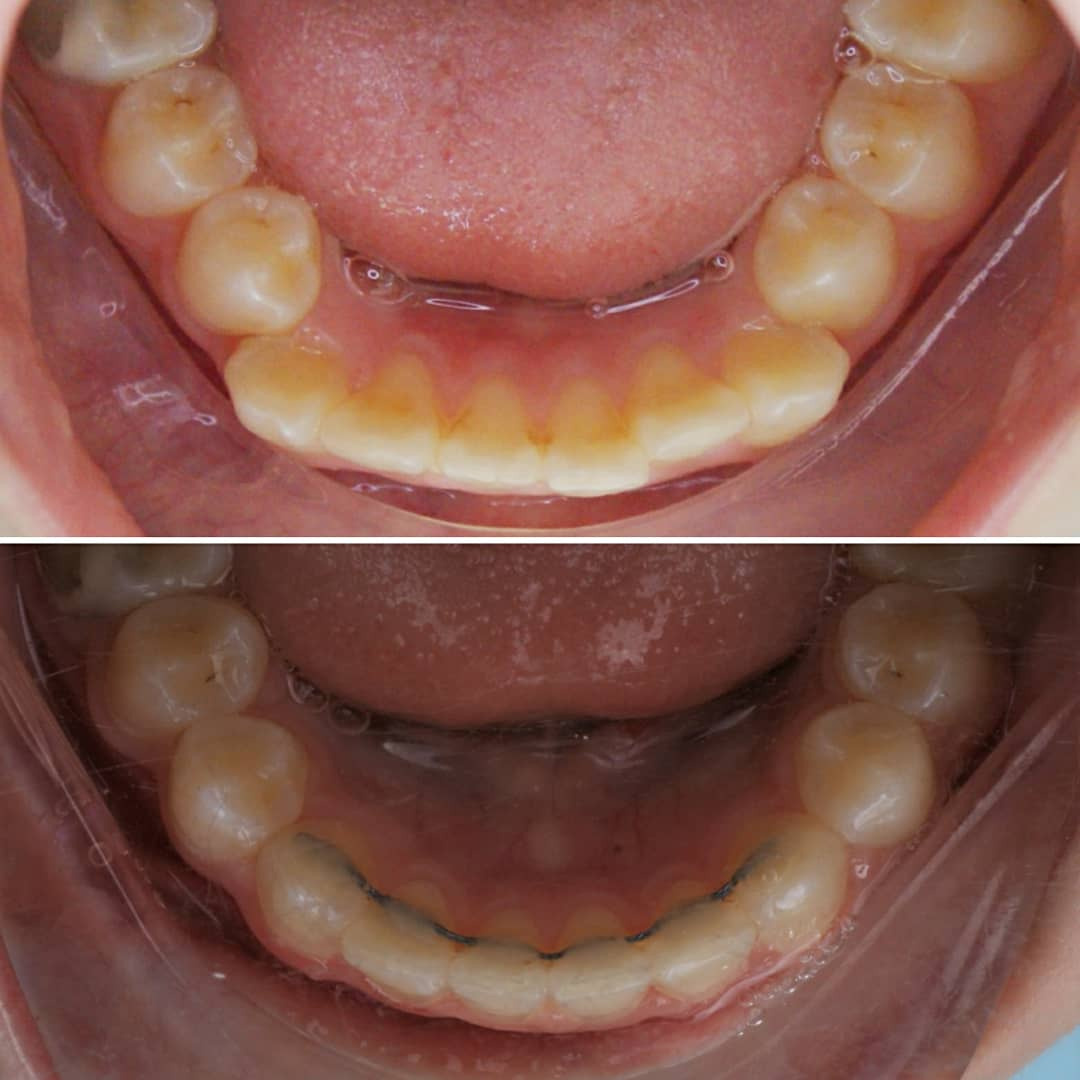

Эта фраза знакома многим ответственным родителям, которые привели на приём к ОРТОДОНТУ своего ребёнка в 5-10 лет, заподозрив проблему или понимая, что места постоянным зубам откровенно не хватает! Горькая правда в том, что брекеты - не волшебное средство от всех проблем, они "расставляют" зубы внутри сформированого объёма челюсти, но никак не влияют на её рост. Родители ждут, а тем временем драгоценное время, когда ребёнок растёт, уходит... Во взрослом возрасте приходится удалять здоровые зубы или прибегать к ортогнатической хирургической операции. 📸 На фото узкая нижняя челюсть, места постоянным зубам нет, боковые резцы прорезываются "вторым рядом".

✅ Помогаем с помощью расширяющей дуги, пружины и зацепных элементов, которые зафиксированы на МОЛОЧНЫЕ зубы